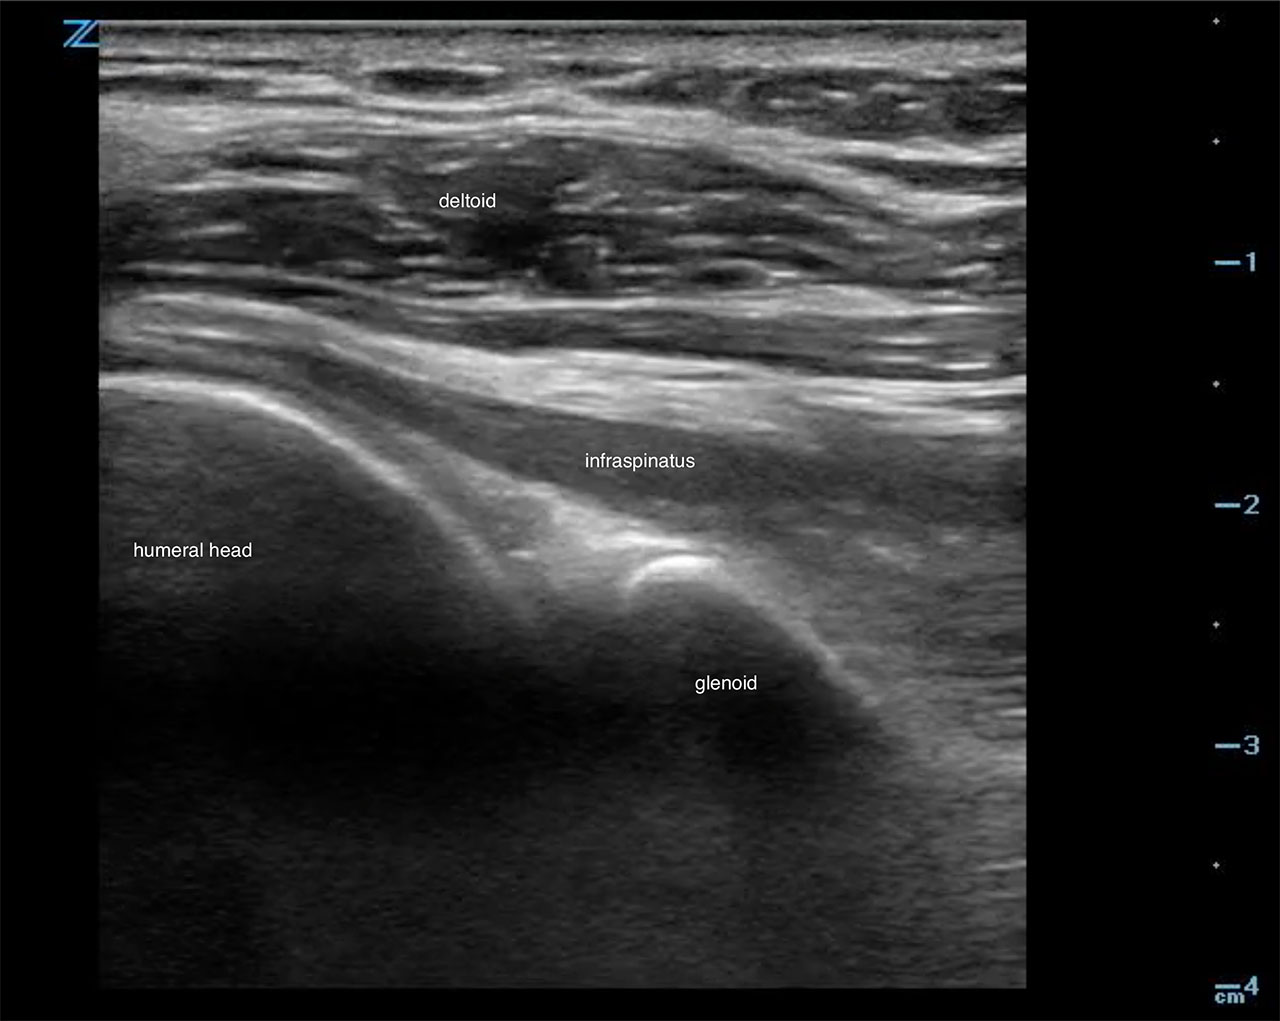

- Scan laterally toward the humerus to obtain a view of the humeral head, glenoid fossa and superficially the infraspinatous tendon.6 (Fig. 9, Video 2)

- Figure 9. Ultrasound demonstrating normal shoulder

- An effusion is an anechoic collection just above the head of the humerus